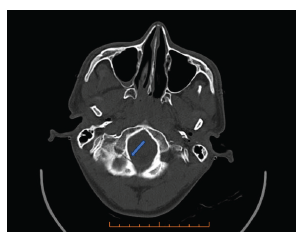

<p>En la evaluación clínica, después de seis horas del evento, se observó un Glasgow de 14/15 y en el examen físico de los pares craneales se constató parálisis facial periférica derecha, con una disfunción grado IV según la escala de House-Brackmann, parálisis del sexto par craneal derecho con imposibilidad para la abducción del ojo (<xref ref-type="fig" rid="f1">figura 1</xref>) y hemiparesia contralateral braquiocrural, con fuerza muscular 3/5, según escala de Daniels, con distribución proximal y distal, sin afectación sensitiva ni alteración de la coordinación; en el resto del examen físico general no se evidenciaron alteraciones. En la tomografía simple de cráneo se observó una fractura lineal no desplazada a nivel occipital derecho, adyacente al agujero magno, sin evidencia de lesiones a nivel del parénquima encefálico (<xref ref-type="fig" rid="f2">figura 2</xref>).</p>

<title>Tomografía axial computarizada simple de cráneo</title>

<attrib>Nota: en la ventana ósea se observa una fractura lineal no desplazada, occipital derecha (flecha azul).</attrib>